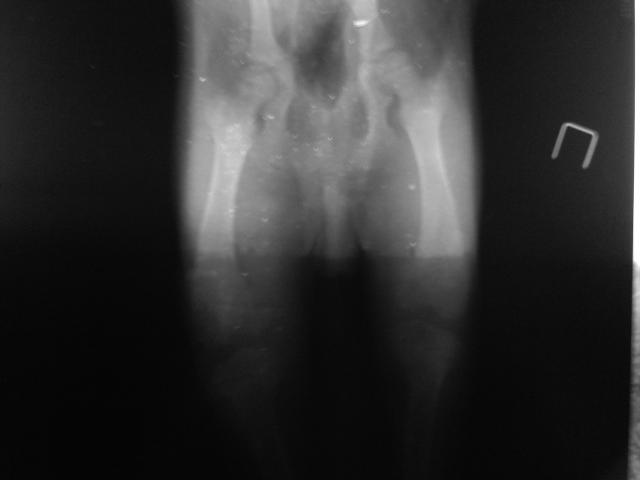

Это фото было сделано пред тем как наложили повязку, после снятия повязки стала еще больше выворачиваться

Видно, что лапка выворачивается не в коленном, а в тазобедренном суставе.Если говорить простым языком, это произошло из-за того что сустав вышел из своей чашечки и теперь находится в не зафиксированном состоянии, как хочет так и выкручивается. Если мы говорим и вывихе, это подразумевает установку сустава на место и наложение тугой фиксирующей повязки, минимум на 7-10 дней, в дополнение к этому противовоспалительные препараты. Если на Римодил появилась такая реакция, возможно, есть смысл, после консультации с лечащим врачом, заменить его на Траумель. Это гомеопатический препарат, практически без побочных эффектов, но достаточно эффективный. Если не сложно, не могли бы Вы выложить фото рентгеновского снимка, сделав его фотографию на стекле окна. Возможно что-то удастся сказать в дополнение. Витамины с хондроитином и глюкозамином обязательно, если вы питаетесь "натуралкой", я бы посоветовала добавить в рацион желатин, но не растворимый! А вываренныый из куриных или говяжих суставов (как на холодец). Получившийся густой бульон можно смешивать с кашей.

Со стороной все понятно. На снимке видно небольшой вывих тазобедренного сустава. В принципе, ничего страшного. Я бы посоветовала полностью отказаться от приема Римадила. К курсу Канвита добавить курс Траумель С, если в таблетках: 1/4 таблетки три раза в сутки за 15 минут до еды, или в виде инъекций: по 0,2 миллилитра подкожно, 1 раз в три дня, курс 2 недели. Раствор можно хранить в шприце в прохладном, темном месте. Что бы уменьшить негативные последствия приема Римадила и поддержать организм, рекомендую Гаммавит по 0,5 мл через день 3-5 дней, подкожно. Повязку, конечно, лучше попробовать наложить, хоть минимальная фиксация сейчас желательна. Что бы было легче можете использовать узкий эластичный бинт.